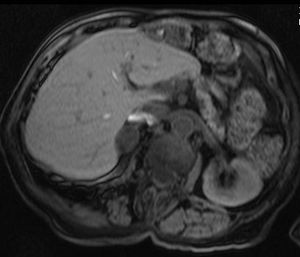

الكظرية

أورام الغدة الكظرية، وغالباً ما تنتشر في البطن، وفي العادة لا يتم التركيز على فحصها؛ وفي معظم الأحيان يتم اكتشافها بطريقة عرضية. واحدة من 10.000 منها خبيثة. وبالتالي، نادراً ما تستلزم أخذ عينة من الورم، خاصة لو كانت الآفة متجانسة وأصغر من 3 سنتيمتر. صور المتابعة لمدة تتراوح من ثلاثة إلى ستة أشهر يمكن أن تؤكد استقرار النمو.

بينما لا تفرز فيه أورام الغدد الكظرية أية هرمونات على الإطلاق، يفرز بعضها الكولسترول، مسبباً متلازمة كوشينگ، الألدوستيرون مسبباً متلازمة كون، أو الأندروجين مسبباً فرط الأندروجينية.